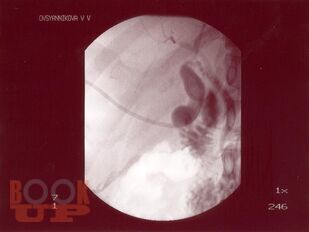

В учебном пособии представлены современные методы лечения ЖКБ. Рассмотрены как хирургические, так и консервативные способы. Показаны их преимущества и недостатки. Также отражены распространенность, патогенез, клиника и диагностика данного заболевания. Пособие предназначено для врачей-терапевтов, врачей общей практики, гастроэнтерологов, врачей скорой помощи, абдоминальных хирургов, интернов, ординаторов.